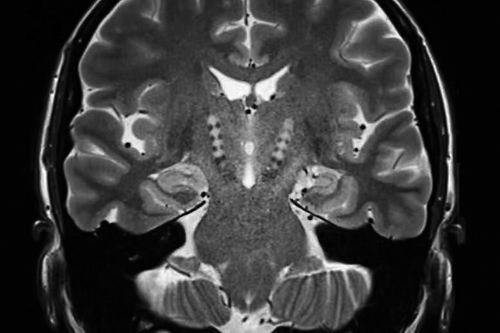

一名58岁帕金森病患者的脑部核磁共振图像 图片来源:ZEPHYR/SCIENCE PHOTO LIBRARY